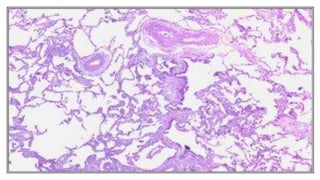

Gas trapping - Hyperinflation

Airflow limitation

Pathology